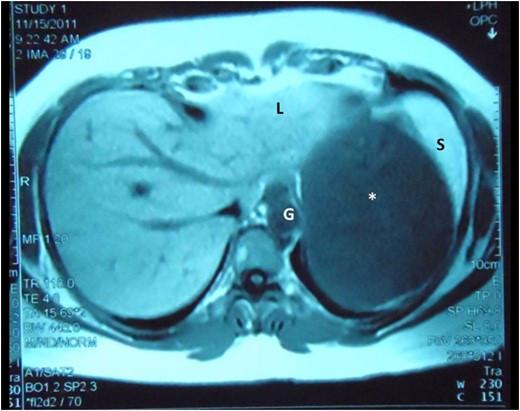

Abdominal MRI demonstrates the cyst (asterisk) intimately related to the left lobe of liver (L), spleen (S) and gastric body (G), still without a clearly demonstrable plane between the structures.

The most accurate modality to diagnose VMCs is probably a MRI with gadolinium [5, 6]. It can also assist in distinguishing Caroli's disease, intra-hepatic cholangiocarcinomas and hepatic metastases [5, 6]. On MRI, they typically appear as hyper-intense, irregularly delineated cysts that do not communicate directly with the biliary tree [6].